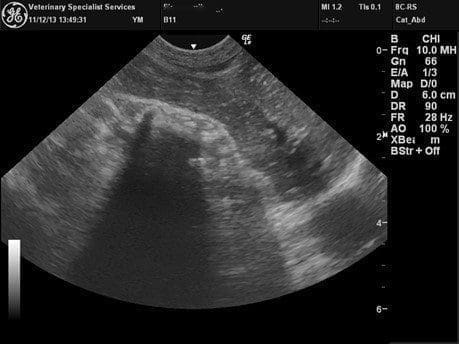

The following abdominal radiographs and abdominal ultrasounds were performed to investigate the cause of the acute vomiting.

Figure 2: Ultrasound image showing curvilinear echogenic interface with complete distal acoustic